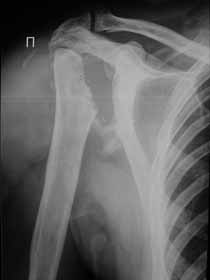

Re: Лизис костей плечевого сустава

Извиняюсь, что-то фотографии сразу не прошли. сейчас исправимся.